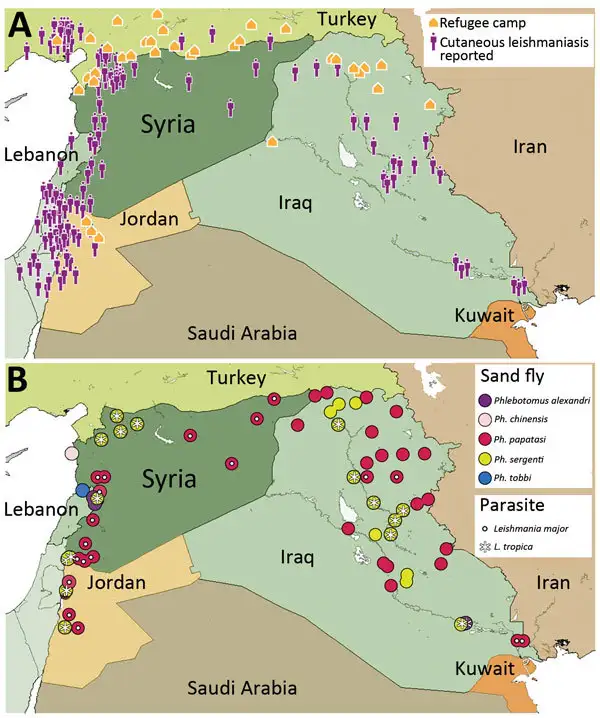

二〇一一年,叙利亚危机爆发。在随后的内战中,数百万人流离失所,医疗系统崩溃,基础设施遭到严重破坏。这些条件为利什曼病的爆发创造了完美的土壤。根据世界卫生组织的数据,叙利亚的利什曼病病例从二〇一〇年的两万三千例激增至二〇一三年的四万一千例以上,而且这一数字很可能被低估。

叙利亚原本就是皮肤利什曼病的流行区。在阿勒颇及周边地区,这种疾病被称为"阿勒颇疖"或"东方疮",有着数百年的流行历史。在正常情况下,公共卫生系统能够有效控制疾病的传播,但战争改变了一切。大规模的人口流离失所使人们暴露于白蛉叮咬的风险中。难民营通常缺乏有效的防护措施,蚊帐稀缺,环境卫生条件恶劣。白蛉的繁殖地——垃圾堆积处、废墟和动物栖息地——在战争区域大量增加。

研究人员对叙利亚的利什曼病爆发进行了深入分析。他们发现,病例的增加不仅发生在叙利亚境内,也影响到邻国。黎巴嫩、土耳其、约旦和伊拉克都报告了来自叙利亚难民或在这些国家工作后返回的叙利亚人的利什曼病病例。在黎巴嫩,皮肤利什曼病病例从二〇一〇年的六例增加到二〇一三年的一千零三十三例,这一剧增几乎完全归因于叙利亚难民。

分子流行病学研究揭示了叙利亚利什曼病爆发的病原体构成。大型利什曼原虫是主要的致病种,占总病例的大多数,但也有相当比例的病例由婴儿利什曼原虫引起。两种寄生虫在临床表现和药物敏感性上存在差异,这对治疗策略的选择有重要影响。婴儿利什曼原虫感染可能导致黏膜受累,需要更积极的治疗,而大型利什曼原虫感染通常局限于皮肤,对局部治疗的反应较好。